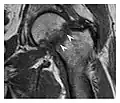

The greater tuberosity of the humerus is also an illustrative location of occult fractures. The osseous injury may follow seizures, glenohumeral dislocation, forced abduction, or direct impaction. They are commonly discovered on MRI in symptomatic patients with suspicion of rotator cuff tear. Coronal images are best suited for detection. They appear as crescentic oblique lines surrounded by a bone marrow edema pattern (Figure 5). The rotator cuff must be inspected since associated ligamentous lesions are common. In the ankle, malleoli and tarsal bones should be checked carefully for any cortical disruptions and radiolucent lines that may reveal a fracture. Awareness of the exact location of the pain will help direct the attention of the interpreter when searching for very subtle signs of fracture (Figure 6).[1]

a

b

Figure 6: Subtle anterior talar fracture in a 39-year-old man presenting with ankle pain after a fall. (a) Anteroposterior radiograph shows a subtle oblique radiolucent line through the talus (white arrows). (b) Sagittal CT reformation confirms the presence of an anterior talar fracture with cortical offset (black arrow). Avulsion fractures, which consist of a detached bone fragment resulting from a ligament or tendon pulling away from the bone, may also present with subtle radiographic signs. Tiny osseous fragments near the presumed attachment site of a ligament suggest this diagnosis. Common sites are the lateral tibial plateau (the Segond fracture), the spinal tuberosity of the tibia resulting from anterior cruciate ligament avulsion, and the ischial tuberosity.[1]

Figure 13: Partial osseous avulsion of the gluteal muscles at the greater trochanter in a 59-year-old man who presented with the right hip pain without a history of trauma. Lauenstein view and anteroposterior and radiographs (not shown) did not show an obvious fracture line or disruption of bony contours in the acetabulum or the right femoral neck. (a) Coronal T1-weighted MRI displays an incomplete fracture line extending partially from the greater trochanter (arrow). (b) Coronal short tau inversion recovery MRI shows heterogeneous hyperintensity in the same region (arrow) as well as hyperintensity within the gluteus medius and minimus muscles (arrowheads) consistent with tissue edema and hematoma.[1]